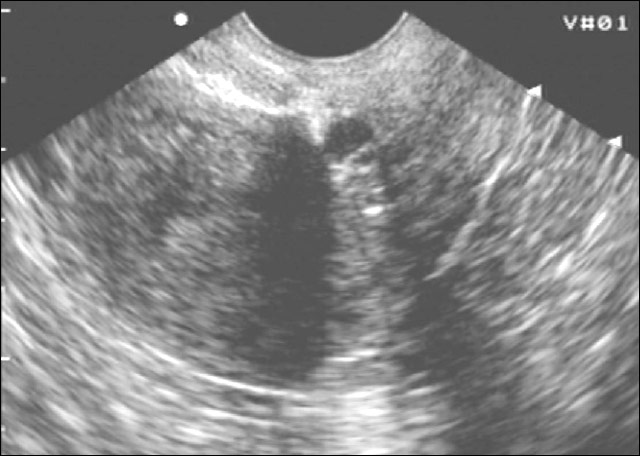

Когда дело доходит до визуализации, этим пациентам обычно назначают трансвагинальное ультразвуковое исследование, чтобы определить, есть ли причина боли в области таза, которую можно визуализировать.Поверхностные имплантаты эндометриоза нельзя увидеть ни на УЗИ, ни на каком-либо другом методе визуализации. Однако эндометриомы часто обнаруживают на УЗИ. Эндометриомы обычно выглядят как простые кисты. Однако их также можно рассматривать как множественные кисты или кистозно-солидные образования. Типичный вид этих поражений на УЗИ демонстрирует низкоуровневые однородные эхо-сигналы, иначе описываемые как внешний вид матового стекла. Это согласуется со старым геморрагическим мусором. Эти поражения также обычно лишены какой-либо васкулярности при исследовании с использованием допплеровского потока.[35] [36]

При глубоком эндометриозе яичников образуются заполненные темной жидкостью полости, которые могут различаться по размеру, известные как эндометриомы или «шоколадные кисты». Диагноз эндометриомы можно заподозрить на основании ультразвукового исследования таза, но окончательный диагноз должен быть основан на микроскопическом исследовании самой кисты.(см. ниже).

- В случае кистозного эндометриоза – эндометриомы, основной метод диагностики –

ультрасонография (УЗИ). Это поможет понять размеры кисты, необходимость делать дополнительные обследования в случае, если есть подозрение на онкологию.